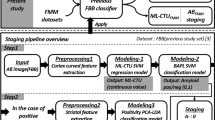

We aimed to quantitatively and qualitatively assess whether there is a discrepancy in detecting amyloid beta (Aβ) positivity between 18F-florbetaben (FBB) and 18F-flutemetamol (FMM) positron emission tomography (PET). We obtained paired FBB and FMM PET images from 107 participants. Three experts visually quantified the Aβ deposition as positive or negative. Quantitative assessment was performed using global cortical standardized uptake value ratio (SUVR) with the whole cerebellum as the reference region. Inter-rater agreement was excellent for FBB and FMM. The concordance rates between FBB and FMM were 94.4% (101/107) for visual assessment and 98.1% (105/107) for SUVR cut-off categorization. Both FBB and FMM showed high agreement rates between visual assessment and SUVR positive or negative categorization (93.5% in FBB and 91.2% in FMM). When the two ligands were compared based on SUVR cut-off categorization as standard of truth, although not statistically significant, the false-positive rate was higher in FMM (9.1%) than in FBB (1.8%) (p = 0.13). Our findings suggested that both FBB and FMM had excellent agreement when used to quantitatively and qualitatively evaluate Aβ deposits, thus, combining amyloid PET data associated with the use of different ligands from multi-centers is feasible.

In the present study, the discrepancy in detecting amyloid positivity between FBB and FMM PET was investigated using visual assessment, SUVR and direct comparison of FBB-FMM Centiloid (dcCL) cut-off categorization. In addition, the discrepancy rate between visual assessment and SUVR cut-off categorization in FBB and FMM was examined. Ideally, histopathological confirmation of Aβ presence in the brain should be the SoT. However, this analysis is rarely achievable because it must be performed post-mortem. Therefore, the false-positive and false-negative rates were compared between the two ligands based on visual assessment and SUVR cut-off categorization as SoT.

Aβ PET imaging analysis

PET images were co-registered to individual MR images normalized to a T1-weighted MNI-152 template using SPM8 in Matlab 2014b (Mathworks, Natick, MA, USA). After standard space registration, the grey matter was divided into 116 regions using the Automated Anatomical Labeling atlas and white matter23. The WC was used as the ROI reference for uptake ratio (which is identical to SUVR) and quantify FBB and FMM retention. Global cerebral cortex amyloid retention ratio was assessed from the volume-weighted average SUVR of 28 bilateral cerebral cortical VOI22,24. The cerebral cortical VOI chosen for this study consisted of the following areas: bilateral frontal (superior and middle frontal gyri; medial part of the superior frontal gyrus; opercular part of the inferior frontal gyrus; triangular part of the inferior frontal gyrus; supplementary motor area; orbital part of the superior, middle, and inferior orbital frontal gyri; rectus; and olfactory cortex), posterior cingulate gyri, parietal (superior and inferior parietal, supramarginal and angular gyri, and precuneus), lateral temporal (superior, middle, and inferior temporal gyri, and Heschl’s gyri), and occipital (superior, middle, and inferior occipital gyri; cuneus; calcarine fissure; and lingual, and fusiform gyri).

Aβ PET positivity based on SUVR assessment

SUVR positivity was classified based on SUVR cut-off value calculated using the iterative outlier approach in different samples consisting of cognitively normal participants over 55 years of age26. To calculate the SUVR cut-off value for Aβ positivity, 171 FMM PET and 202 FBB PET scans were evaluated. Consequently, when WC was used as the reference region, the cortical SUVR cut-off value was 1.1 for FBB and 1.03 for FMM.

For direct comparison of the FBB-FMM conversion method, SUVR values for the FBB-FMM cortical target volume of interest (CTX VOI) were directly converted into CL units using the dcCL method based on the CL conversion equation below11,27,28:

where SUVRind represents the individual SUVR values of all YC-0 and ADCI-100 participants, and SUVRYC-0 and SUVRADCI-100 represent each group’s mean SUVR values. The CL equation was derived for FBB and FMM PET separately and applied to the FBB and FMM SUVR, respectively, from the FBB-FMM CTX VOI. The SUVR from the FBB-FMM CTX VOI used to determine dcCL was termed dcSUVR. When WC was used as the reference region, the dcCL cut-off value was 24.9 dcCL units for FBB and 15.1 dcCL units for FMM.